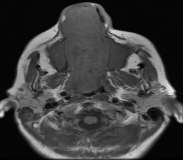

En RM, secuencia en T1, la lesión se observa hipo-isointensa y se proyecta desde orificio nasal hasta Cavum y coana, con aspecto de lesión solida expansiva ubicada sobre seno maxilar derecho que se extiende alrededor de la pared interna del seno nasal hacia la fosa nasal homolateral y se proyecta hasta senos frontales y presenta erosión de la lámina papirácea (Figura 5 – 6 – 7).

En secuencia T2 sin contraste, la lesión presenta áreas hiperintensas y de baja señal, determinando marcado desplazamiento del tabique nasal y oblitera trompa de Eustaquio derecha, con ocupación de celdillas mastoideas y oído medio homolaterales (Figura 8–9-10).